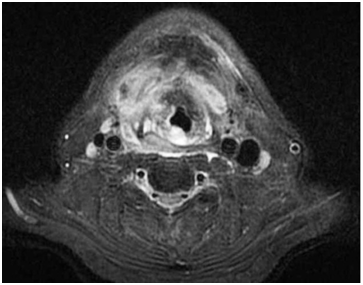

50years old male patient referred to emergency department complaining from dysphagia and sore throat. In history it was learned that he has been living in a refugee camp. He had chronic hepatitis C infection and drug addiction. In physical examination; swelling occupying the pharyngeal cavity, fever 38.4 Celsius and dyspnea was noted. Poor oral hygiene was observed. A neck computer tomography imaging of the neck was planned and it was reported as retropharyngeal abscess (Figure 1). Respiratory arrest occurred while the patient was being transferred to emergency operating room for abscess drainage and a tracheotomy was performed. After tracheotomy abscess drainage was performed under general anesthesia in Trendelenburg position. He was observed in intensive care unit for two days after surgery and transferred to ear nose throat clinic. After 7days follow up the retropharyngeal abscess was not recovered and a second intervention and abscess drainage was performed on seventh day. The patient was decannulated on postoperative first day and discharged with full recovery.

Figure 1 Neck CT; Airway obstruction and air traps in retropharynx.